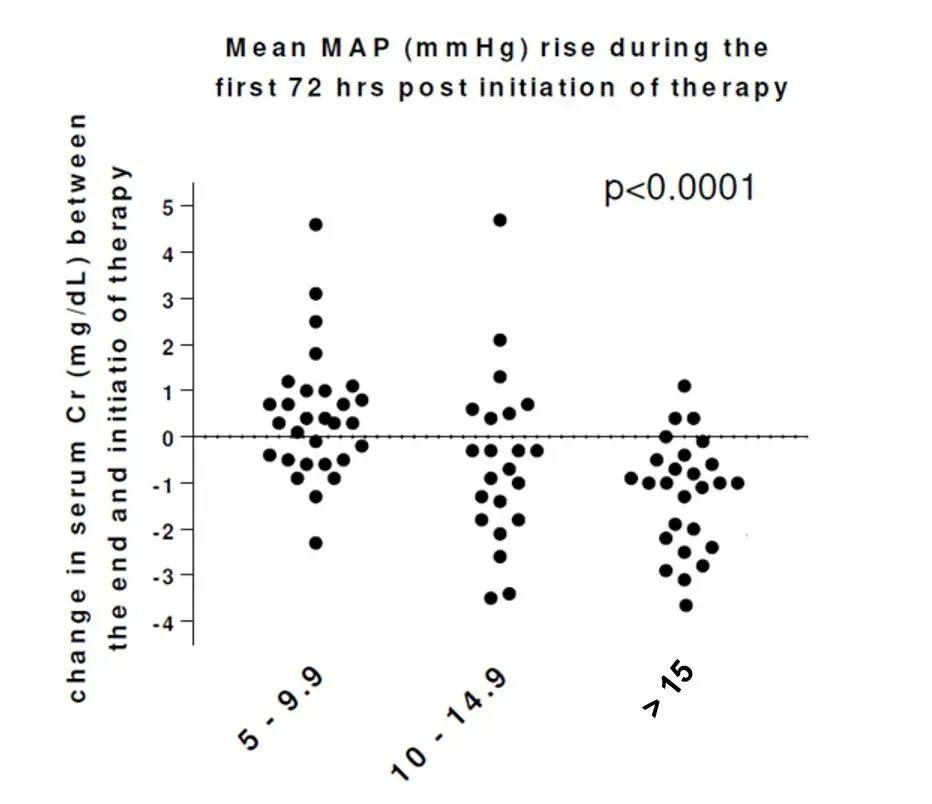

Síndrome Hepatorrenal: Os Diuréticos Têm Lugar no Tratamento?

Síndrome Hepatorrenal: Os Diuréticos Têm Lugar no Tratamento?Síndrome hepatorrenal tipo 1 e diuréticos: um novo paradigma? Descubra como a combinação de norepinefrina e furosemida pode transformar o manejo da síndrome hepatorrenal tipo 1!

Valkercyo Feitosa

2 anos atrás